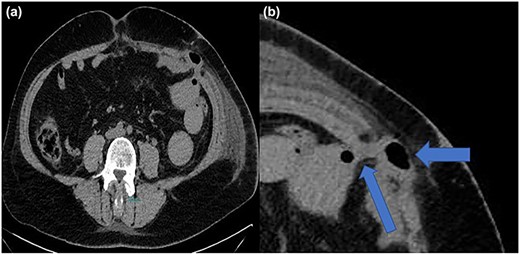

A 48-year-old woman was admitted to our department in order to have laparoscopic repair for a symptomatic umbilical hernia. The patient suffered for allergic asthma. Three ports were inserted, two 10-mm ports at the left lateral abdomen, and one port 5 mm at the right lateral abdomen. The next day the patient was discharged with no complications. The second postoperative day the patient reported diffuse abdominal pain, constipation, nausea and vomiting. An abdominal X-ray was carried out, without any useful information. Abdominal computed tomography revealed the small bowel herniation (Fig. 1a) through the 10-mm trocar at the left lateral abdomen (Fig. 1b).

(a, b) Computed tomography imaging with TSH and intestinal involvement (blue arrows).